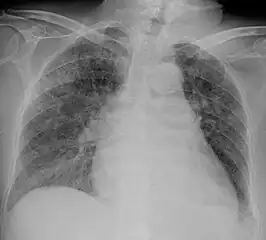

Tuberculosis of the lungs